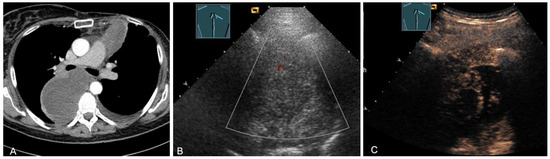

Figure 1.

A patient after surgery for a bronchial carcinoma with a palpable chest wall tumor (A). B-mode US reveals a heterogeneous echogenic mass (B) without enhancement on CEUS (C), consistent with hematoma of the chest wall.